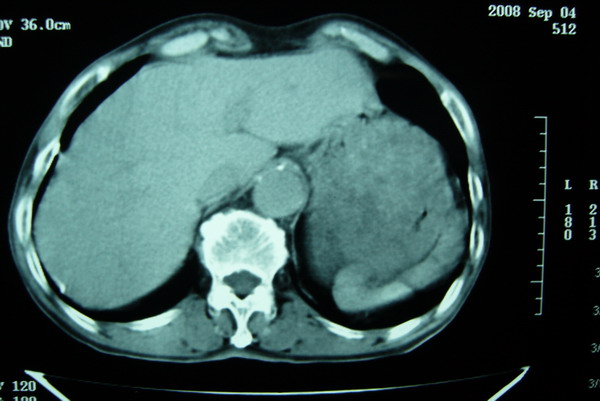

标题: CT15579:男 86岁 咳嗽 咳少量白痰 发热2天 吸烟史60年 [打印本页]

标题: CT15579:男 86岁 咳嗽 咳少量白痰 发热2天 吸烟史60年

右肺上叶巨大软组织肿块,轮廓不规则,纵隔内有肿大淋巴结,首先考虑肺癌。

右上肺一不规则团块,边缘有分叶和毛刺,纵隔有淋巴结肿大。右肺周围性肺癌首先考虑。